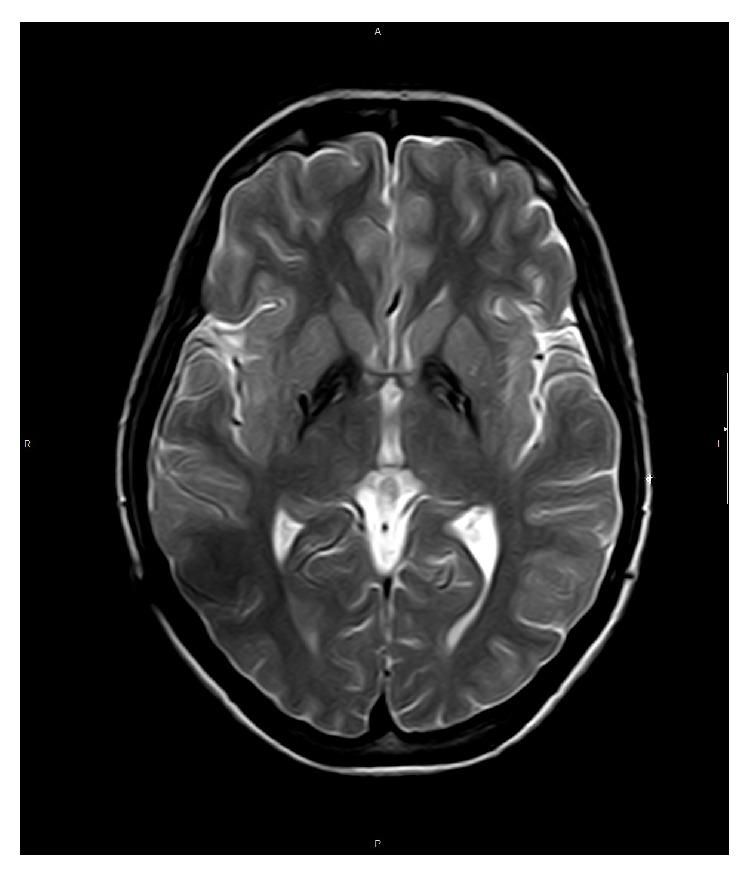

Pantothenate kinase-associated neurodegeneration (PKAN) is usually associated with dystonia, which is typically severe and progressive over time. Pallidal stimulation (GPi DBS) has been carried out in selected cases of PKAN with drug-resistant dystonia with variable results. We report a 30-month follow-up study of a 30-year-old woman with PKAN-related dystonia treated with GPi DBS. Postoperatively, the benefit quickly became evident, as the patient exhibited a marked improvement in her dystonia, including her writing difficulty. This result has been maintained up to the present. GPi DBS should be considered in dystonic PKAN patients provided fixed contractures and/or pyramidal symptoms are not present.

https://cdn.ncbi.nlm.nih.gov/pmc/blobs/94f7/4352941/beece40d8299/CRINM2015-245735.001.jpg